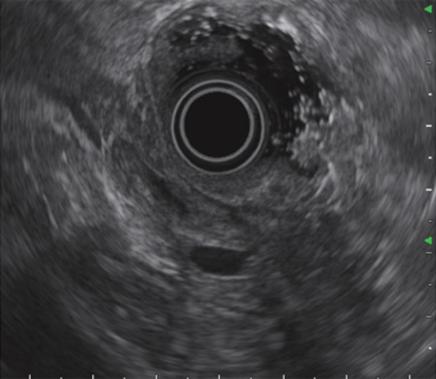

超声内镜(EUS):即内镜和超声相结合的消化道检查技术,将微型高频超声探头安置在内镜顶端,当内镜插入体腔后,在内镜直接观察消化道黏膜病变的同时,可利用内镜下的超声行实时扫描,可以获得胃肠道的层次结构的组织学特征及周围邻近脏器的超声图像,从而进一步提高内镜和超声的诊断水平。

简单来说,医生在使用超声内镜进行检查时,发现病灶,可直接诊断病变的起源层次,并可根据大小、回声特点等初步判定肿瘤性质,是生理性改变还是病理性改变,是器质性改变还是功能性改变等等。

电子凸阵扫描

电子环形扫描